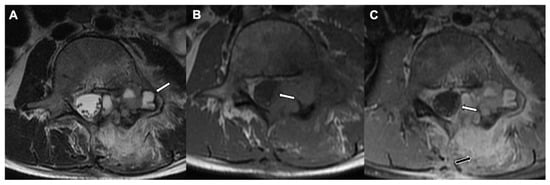

6. Osteoblastoma

| Radiographic/CT features | Juxtacortical, well-circumscribed homogenous sclerotic lesion | Homogenous intra-medullary sclerotic focus with spiculated margins | Small (less than 2 cm) cortical lucency with extensive surrounding sclerosis | Expansile large (more than 2 cm) lucent lesion with matrix mineralization |